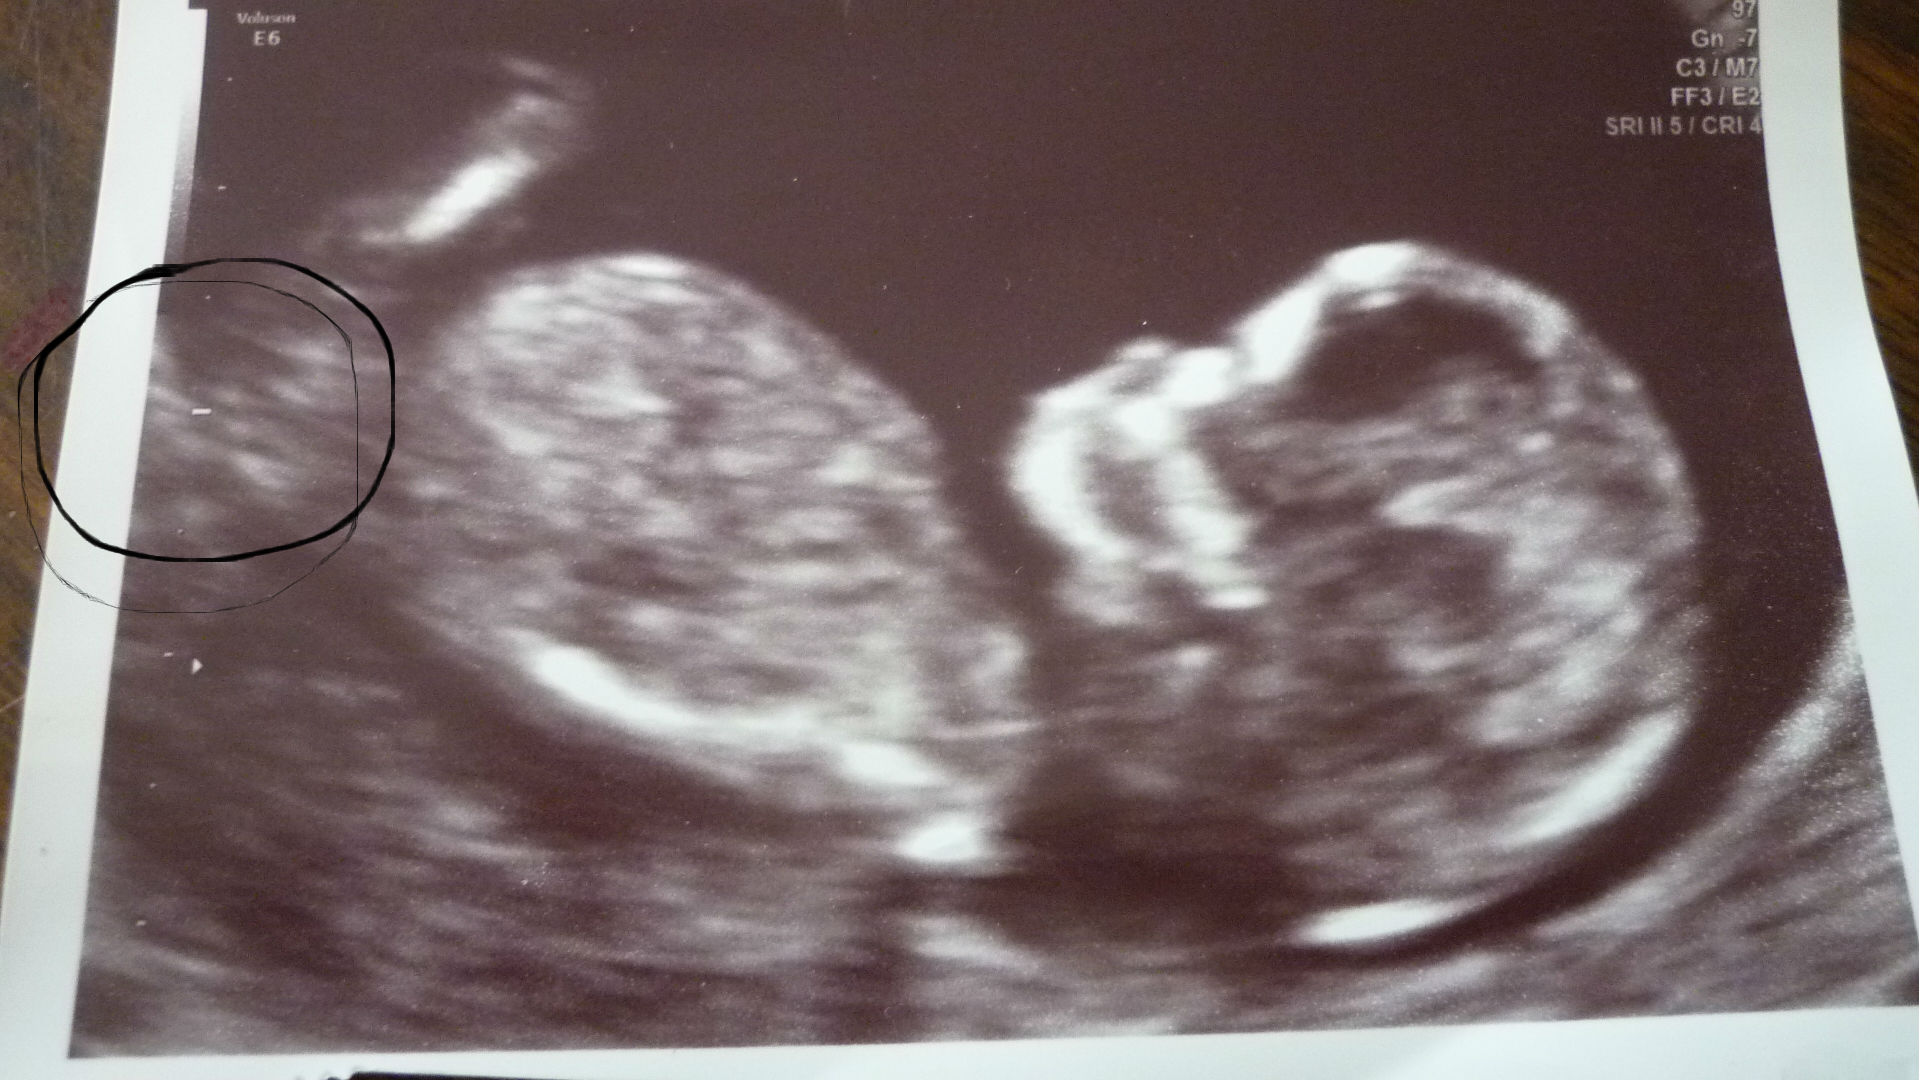

Attachment 33343 do you no if this is the nub that i have circled??